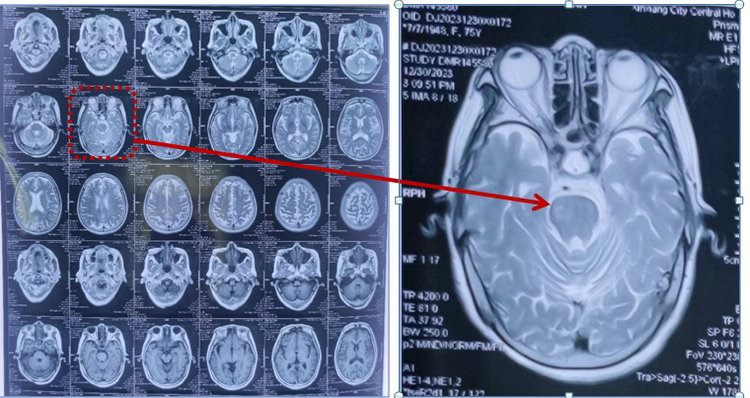

74岁的朱女士于2月余前被诊断为脑干梗死,在老家医院康复科住院治疗,1月余前左肩出现疼痛伴关节活动度受限,继续在该医院治疗无效后,经多方打听转入郑州大学五附院康复医学科。

入院后经专科查体及辅助检查后,考虑该患者为肩关节半脱位合并肩袖损伤、左侧肱二头肌长头肌腱腱鞘炎。诊断明确后,为该患者制定康复目标(强化左侧肩关节稳定性、缓解左肩关节疼痛、提高肢体实用性),并根据该目标为患者制定了个体化康复治疗方案。经一个疗程的治疗,患者左肩关节疼痛较前减轻,夜间睡眠质量也得到显著改善,左上肢实用性有所提高,可以拿馒头送到嘴里,达到患者目标,出院回家。

包括疼痛性质评价、肩关节外观、肩关节活动、肩部超声、肩关节磁共振、心理评估。